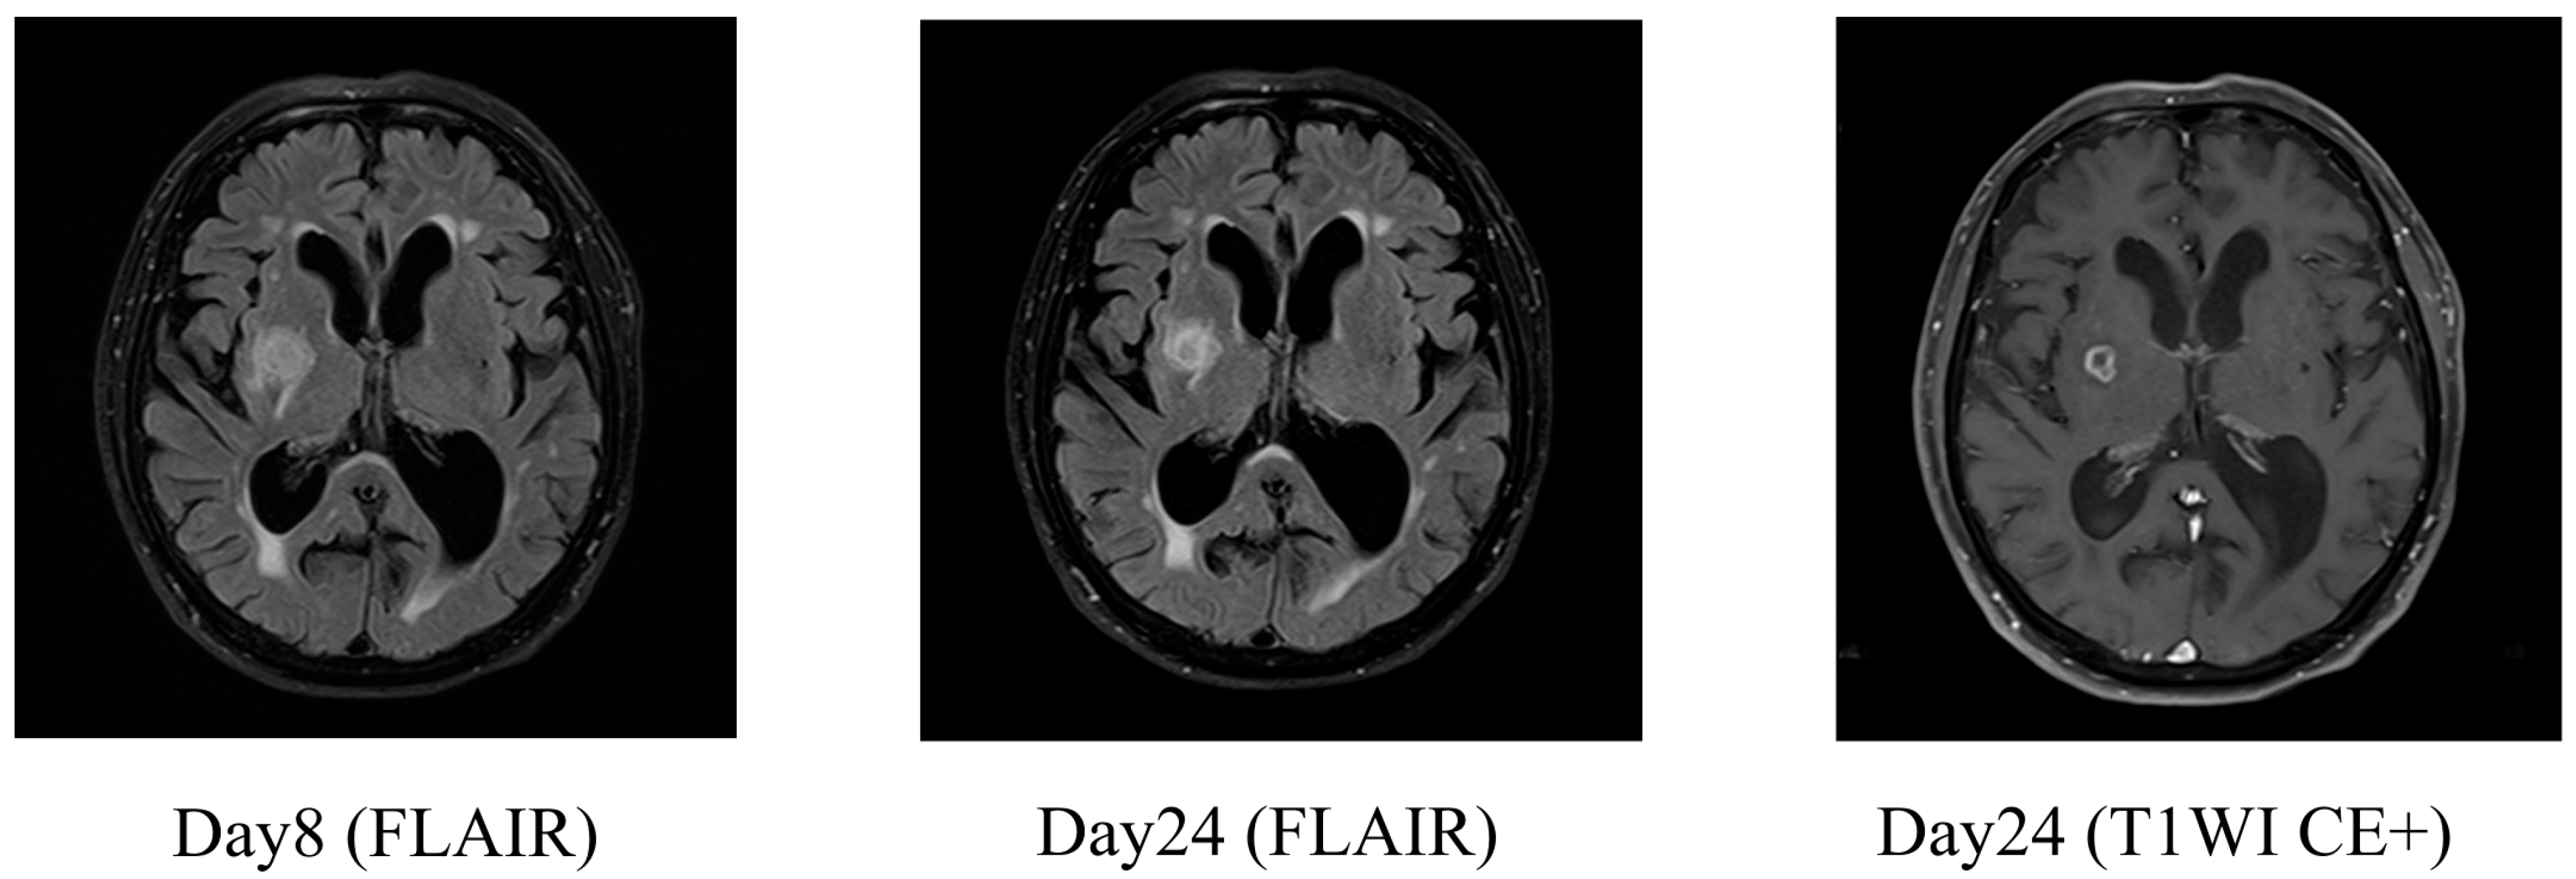

2.1. Case 1